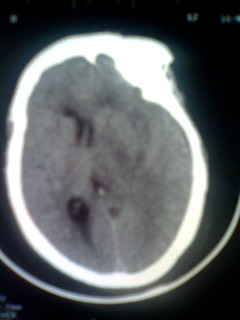

女。65岁头疼,多发硬化病史5年,近十余天加重

巨大囊性占位,白质水肿确不明显,定性?

囊实性占位,考虑胶质瘤可能性大,建议增强.

北京天坛,结论:多发硬化